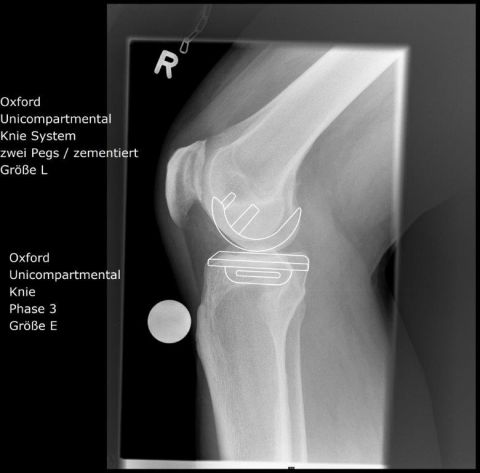

KNIEHALBGELENK - SCHLITTENPROTHESEN

In bis zu 20 -30 % der Fälle kommt es nur zu einer einseitigen, meist innenseitigen Abnutzung des Kniegelenkes. Die Außenseite des Gelenkes zeigt sich noch in einem guten Zustand. Oft sind mit diesem Verschleißmuster O-Beinachsenabweichungen verbunden. Die Verwendung von künstlichen Halbgelenken ermöglicht es, den noch gut erhaltenen Kniebereich zu erhalten. Die Funktion des Kniegelenkes mit den eigenen Kreuzbändern ist dabei besonders gut.

Wir verwenden ein Implantat mit einem mobilen Inlay (Oxford-Schlitten), wodurch die komplexe Bewegung des Beugens und Streckens des Kniegelenkes mit dem „Roll back“-Mechanismus der Oberschenkelrolle durch den Gleitmechanismus in der Prothese besonders gut umgesetzt werden kann.

OXFORDSCHLITTEN

innenseitige Kniegelenksarthrose

OP Planung

Nach der OP (Oxfordschlitten)